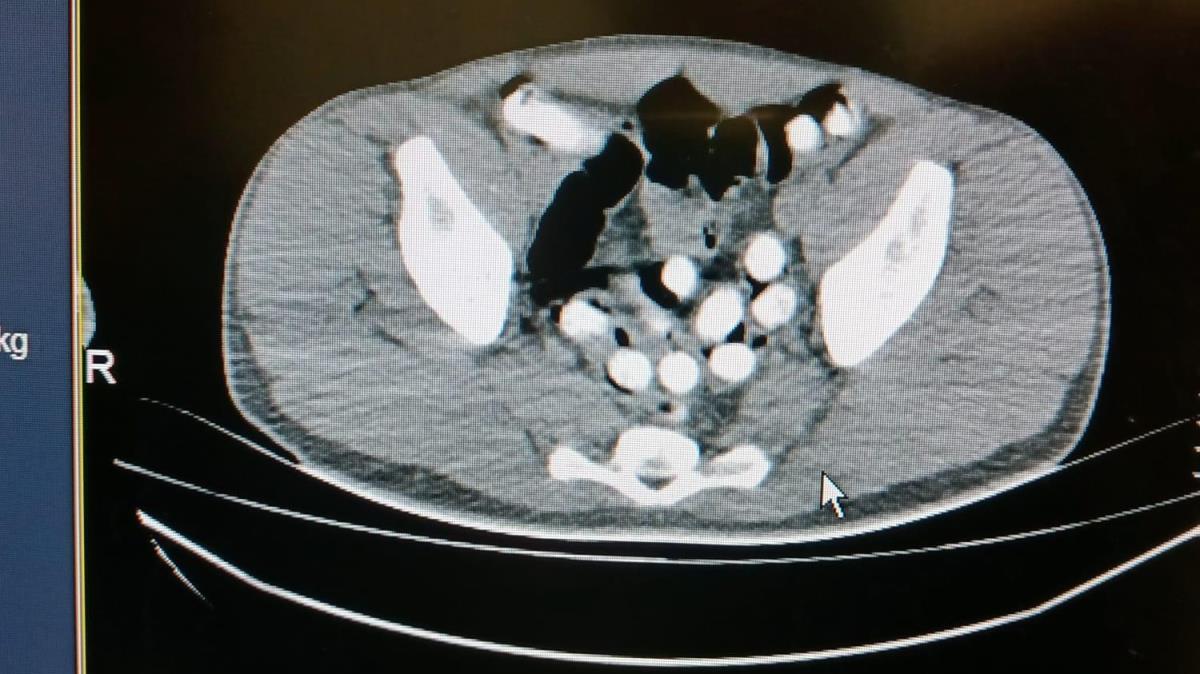

İl Emniyet Müdürlüğü Narkotik Suçlurla Mücadele Şube Müdürlüğü ekipleri, uygulama noktasında durdurulan otobüste yolculuk eden İranlı M.H.'nin üzerini aradı. Polisin midesindeki şişlikten şüphelendiği M.H., 6 kapsül halinde 62,35 gram afyon sakızını kustu. Hastaneye götürülen M.H.'nin çekilen röntgeninde mide ve bağırsak kısmında başka kapsüller bulunduğu da görüldü. Ek gözaltı süresi alınan şüpheli, doğal yollarla mide ve bağırsağındaki afyon sakızlarını çıkardı.

Midesinden 102 kapsül halinde 1 kilo 126 gram afyon sakızı çıkarılan şüpheli, sevk edildiği adliyede çıkarıldığı hakimlikçe tutuklandı.